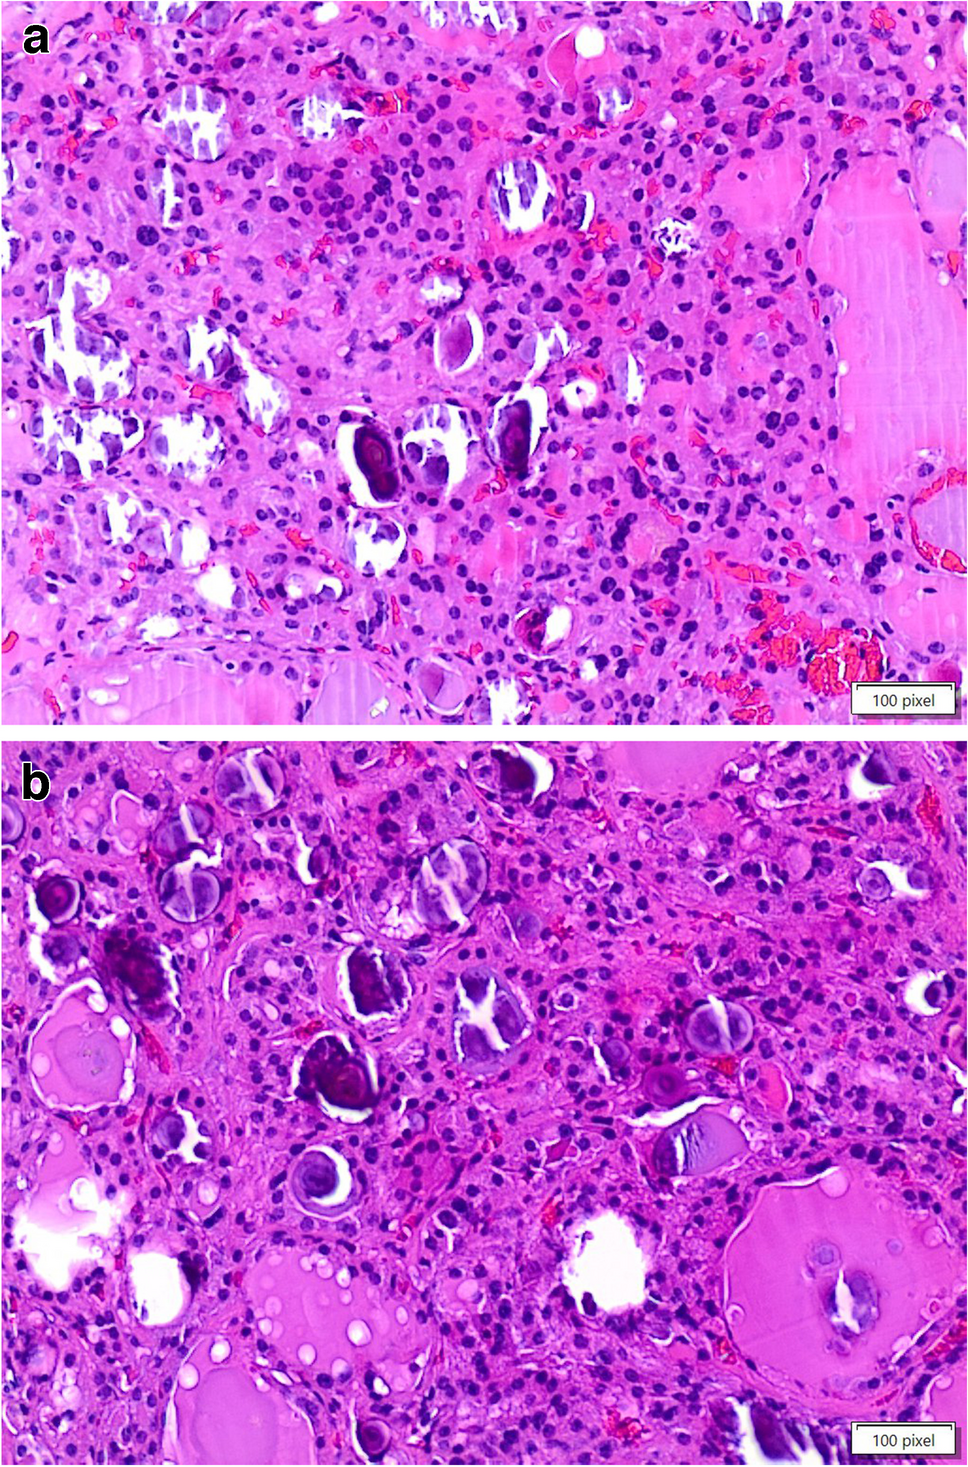

The diagnoses included 12 adenomas (one follicular and 11 oncocytic adenomas, Fig. 1A–B and Fig. 3), two chronic lymphocytic thyroiditis (HT) including one case with extensive oncocytic metaplasia, and 12 cases of thyroid follicular nodular disease (TFND) (Table 1, Fig. 2). In 24 of 26 cases, the thyroid parenchyma was entirely included at various levels, to find sub-centimeter PTC which had been missed in the first evaluation (Table 2). In the remaining two cases (one oncocytic adenoma, one follicular nodular disease), the nodules with psammoma bodies were entirely embedded (Fig. 3). None was found to harbor carcinoma after detailed sectioning. None of the patients have shown any evidence of thyroid carcinoma on follow-up.

Fig. 2

The picture shows the evidence of psammoma bodies in the contest of a thyroid follicular nodular disease (H&E, 200 ×)

The PBs were found in the thyroid parenchyma in case of thyroid follicular nodular disease and thyroiditis, and within the adenomas, particularly oncocytic adenomas. Specifically, in the cases with chronic lymphocytic thyroiditis, PBs were seen close to the foci of oncocytic metaplasia.